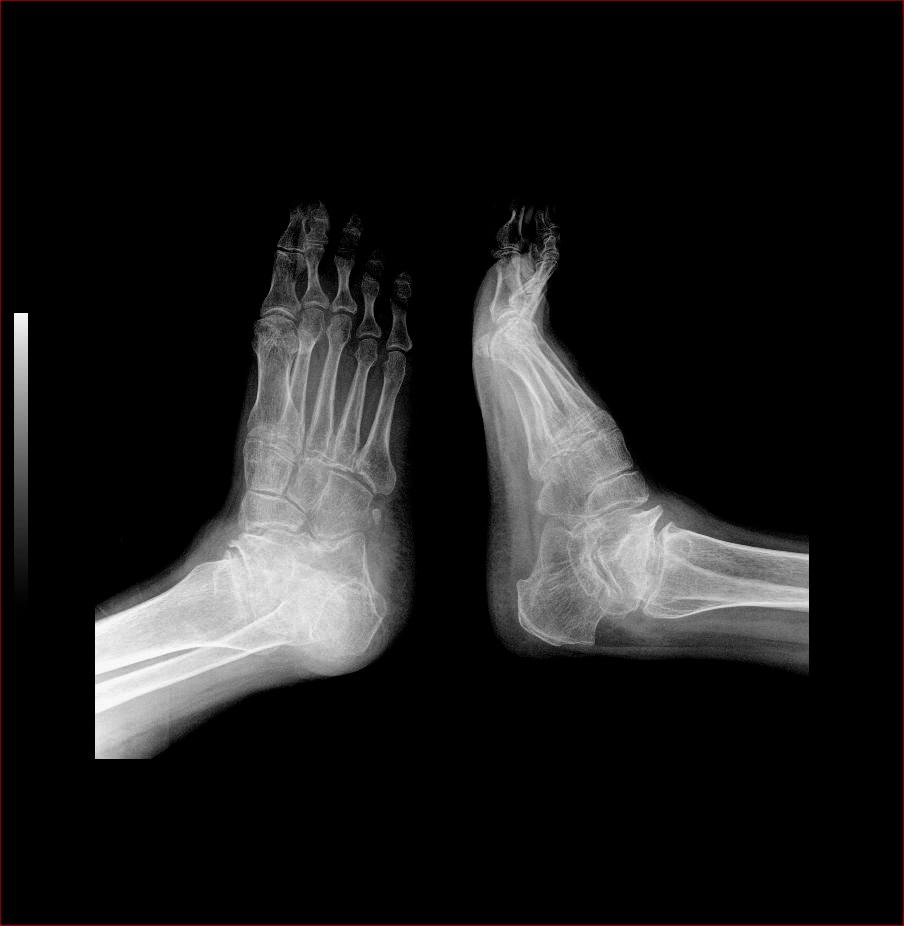

以下是引用杏林古木在2008-4-26 18:31:00的发言:[br]大骨节病。

以下是引用yangyudong333在2008-4-27 6:28:00的发言:[br]跟骨短,矩骨扁,符合大骨节病

以下是引用光影相伴在2008-4-26 18:32:00的发言:[br]考虑:大骨节病。